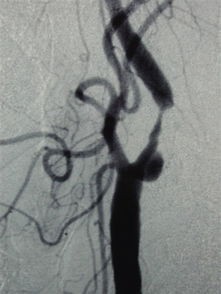

患者老年男性,65岁 主诉:体检发现双侧颈动脉狭窄5月余 现病史:患者5月前于当地医院体检发现双侧颈动脉狭窄,行颈动脉椎动脉彩色多普勒超声检查,提示双颈动脉狭窄,行头部CTA,提示左侧颈动脉重度狭窄,给予阿司匹林,立普妥、波立维口服。 既往史:既往体健

查体:双侧颈动脉无明显扩张,听诊左侧颈动脉可闻及收缩期杂音,右侧颈动脉、锁骨下动脉区未及明显杂音 辅助检查:超声提示:左侧颈总动脉多发斑块,较大者位于分叉外侧壁,斑块表面可见凹陷,至颈总动脉分叉近重度狭窄。右侧颈总动脉分叉延至颈内动脉起始前壁低回声斑块。

诊断:双侧颈动脉狭窄 治疗:颈动脉内膜剥脱术